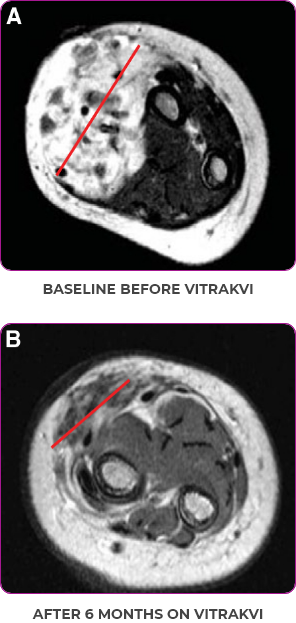

Reduction in tumor burden1

MRIa imagery of the brain. Red line indicates the maximum dimension.1

aMRI, magnetic resonance imaging.

Pre- and post-treatment imaging, by DuBois SG et al, is licensed under CC BY 4.0.

aIFS, infantile fibrosarcoma; MRI, magnetic resonance imaging; pCR, pathological complete response; PR, partial response.

Response to VITRAKVI1

- Patient achieved a confirmed partial response after 4 cycles of VITRAKVI with a 45% reduction in tumor burden

- Following 6 cycles of VITRAKVI, the patient was referred for definitive limb-sparing surgery

- Pathology revealed a complete pathologic response and clear resection margins with scar tissue noted